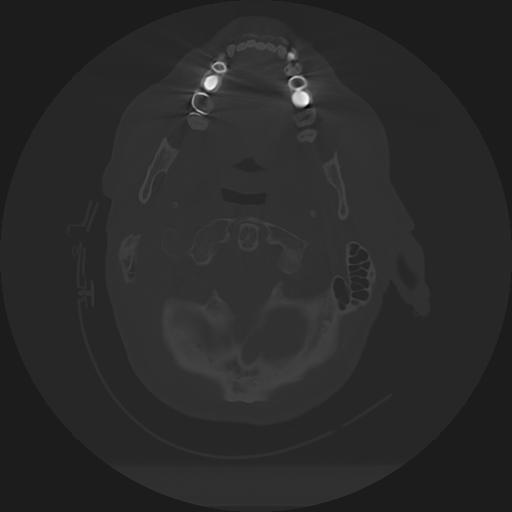

11 HUESO,,Axial,2.0,HUESO,,